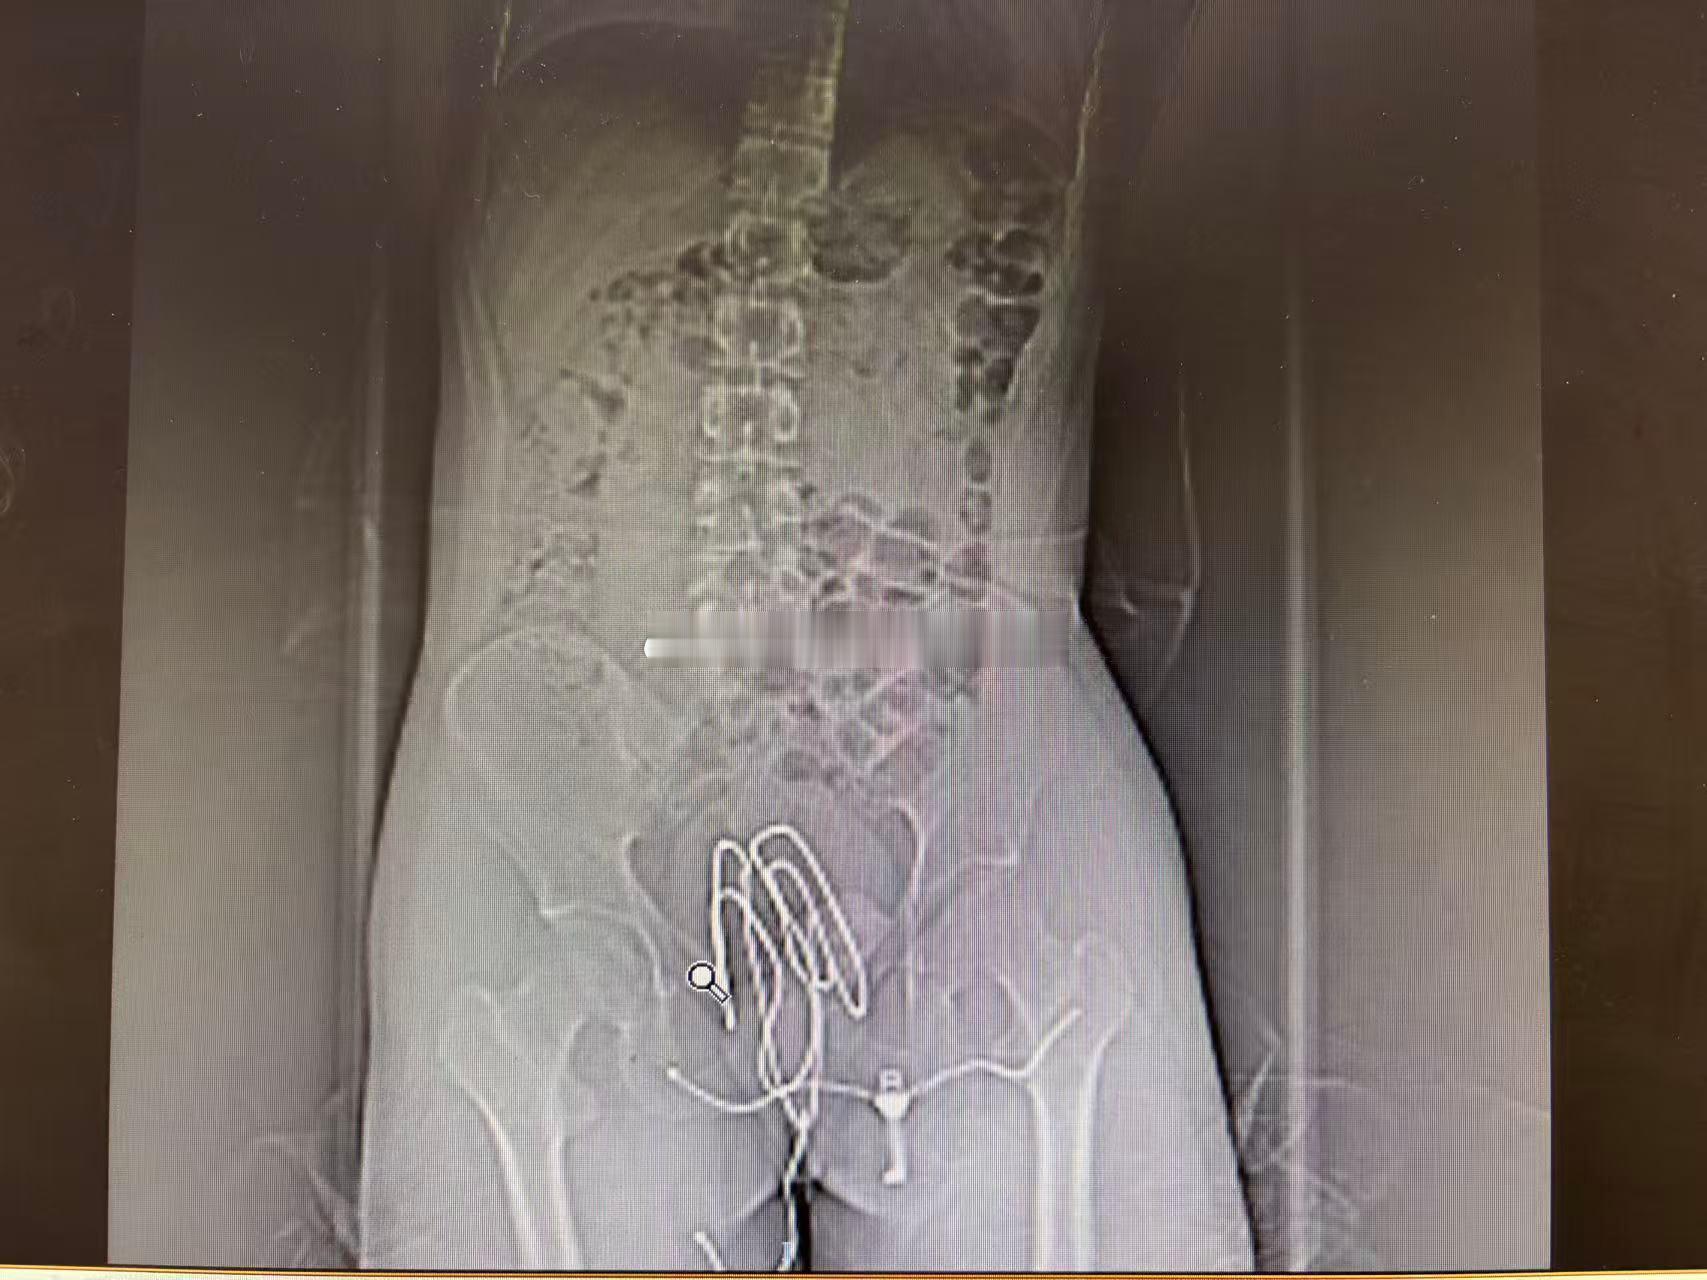

投稿:接了个直肠异物的,18岁小伙子,把晾衣撑子塞进去了。。。